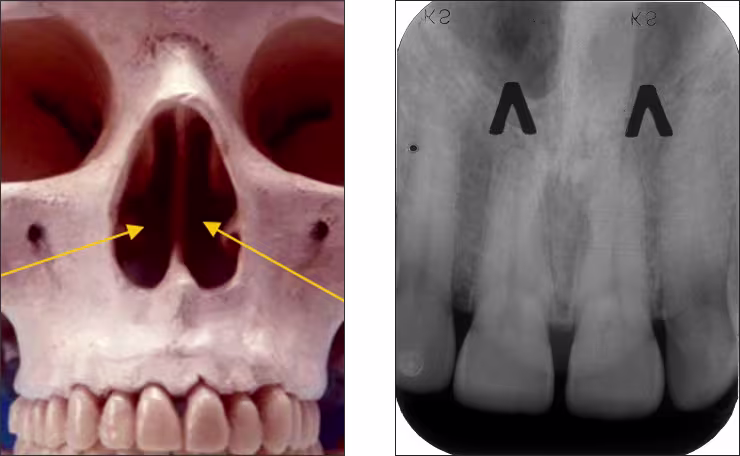

Nasal fossae – The nasal fossae (plural; singular - fossa) are the nasal openings located above the maxillary anterior teeth. The fossae are divided in the midline into right and left chambers. Radiographically, the nasal fossae appear as vertically oblong radiolucent structures bounded by bone. These structures can be seen on maxillary central incisor periapical views and partially on lateral incisor and canine periapical images.

Nasal septum – The nasal septum is a bony vertical band-like midline structure that divides the nasal cavity into right and left chambers. The nasal septum is a radiopaque landmark visible on maxillary central incisor periapical images.

Anterior nasal spine – The anterior nasal spine (ANS) is a bony projection located at the base of the nasal septum in the maxillary midline. Radiographically, the ANS appears as a V-shaped or triangular point radiopacity. This structure is recorded on maxillary central incisor periapical images.

Inferior nasal concha – The inferior nasal concha or turbinate bone projects into the inferior aspect of the nasal fossa from the lateral walls of the nasal cavity. These bilateral radiopaque structures (conchae) are sometimes visible on central and lateral incisor periapical images.